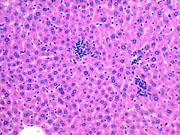

Microgranulomas consisting of mononuclear inflammatory cells and associated with hepatocyte necrosis are commonly seen in mouse liver.